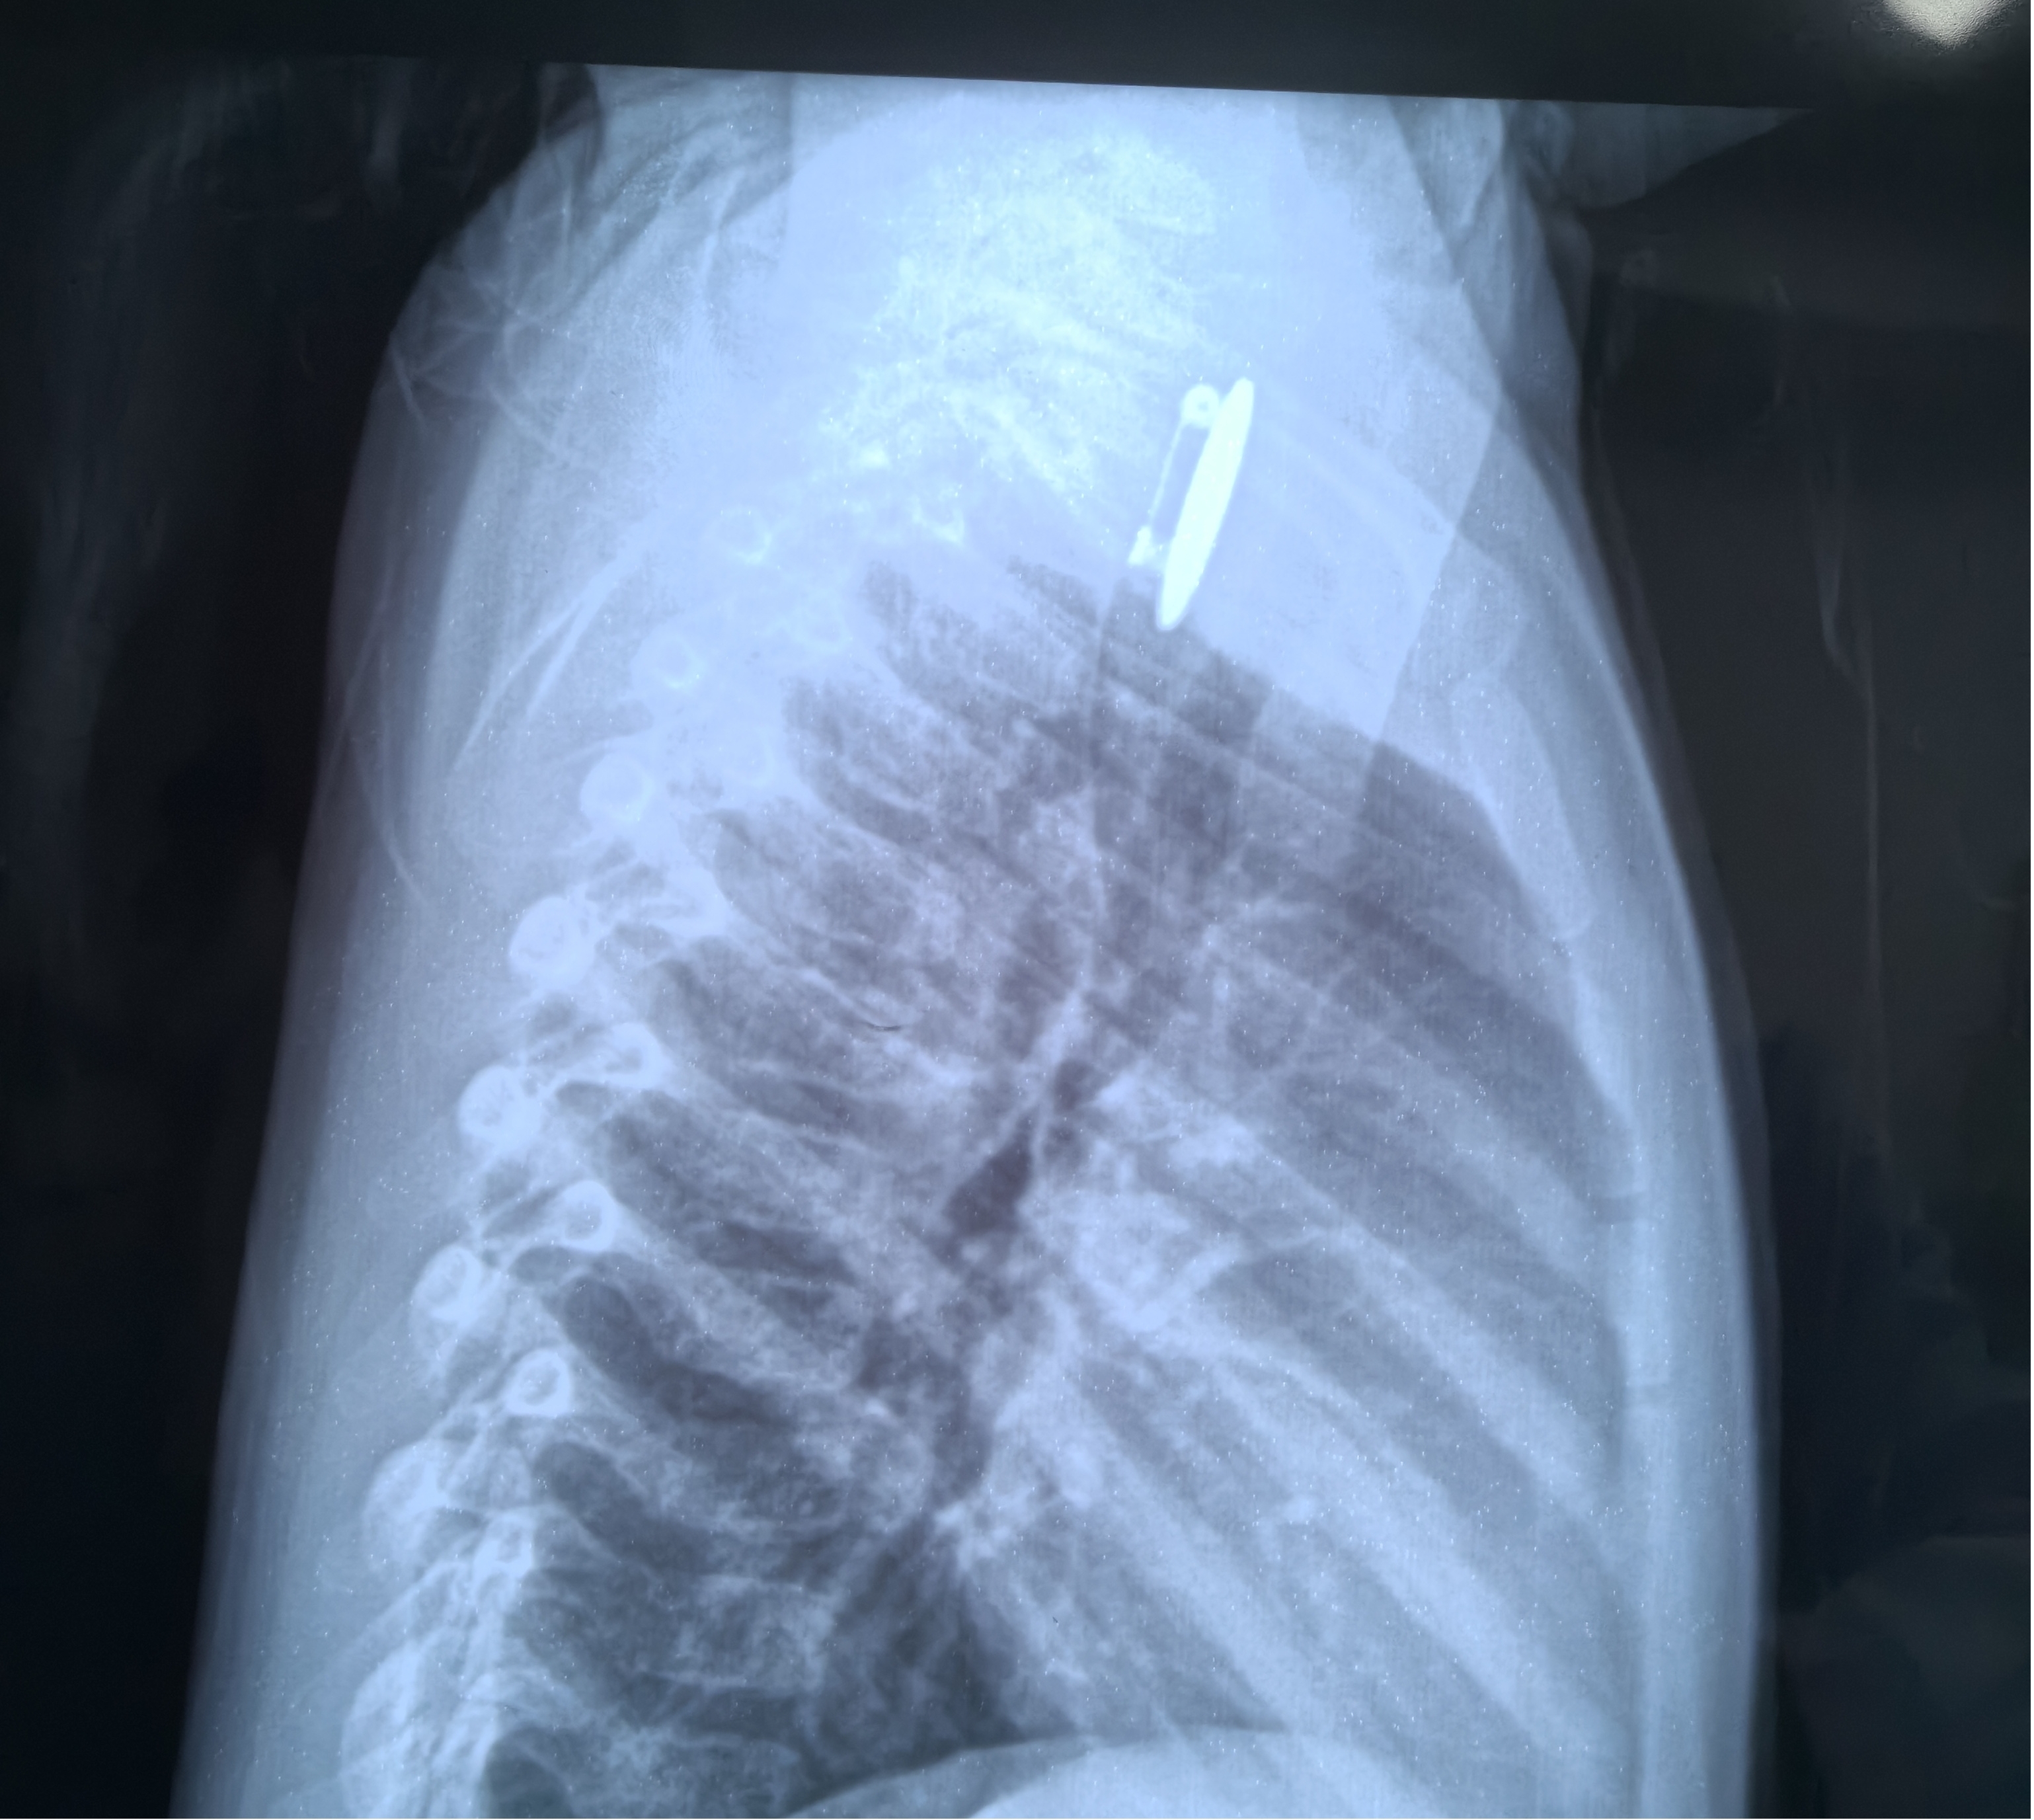

11月21日22点左右,家住长沙县1岁11个月的女孩小钰,在床上开心的玩着一枚像章,这时妈妈为了让孩子睡觉,准备把孩子手上的像章拿走,孩子攥着它不肯撒手,拉扯间,小钰急忙塞进嘴里。家长立即带孩子前往当地医院,胸片提示“食管内异物”,又急急忙忙于凌晨1点转诊到了湖南省儿童医院耳鼻咽喉头颈外科,值班医师在完善术前检查后,在急诊全麻下为她实施了食管镜检加异物取出术,术中顺利取出了一枚完整的圆形像章。所幸的是像章的别针处是关闭的,否则可能刺伤周围组织。

食管异物是是儿童常见的一种急症。食管误吞异物后可出现吞咽困难、流口水、吞咽疼痛、拒食,当异物较大压迫气管时还有可能出现呼吸困难、咳嗽等,严重者可并发食管炎、食管穿孔等并发症,尖锐及腐蚀性异物有可能刺破或腐蚀血管导致大出血,而危及生命。